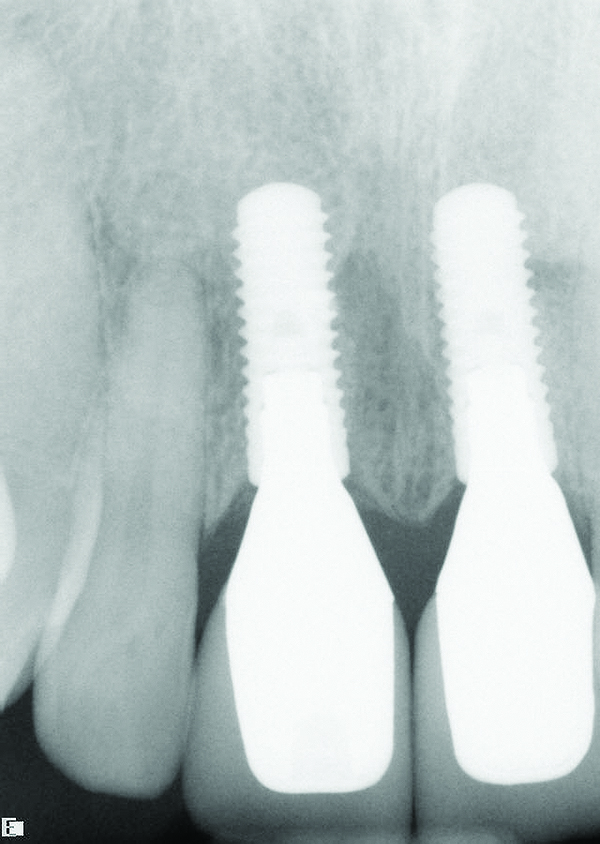

Fig 3. Radiograph confirming that the implant placement matched the presurgical plan.

Figure 3

Fig 4. Radiograph taken on the day of delivery of the final implant-supported restorations, 3 months after implant placement.

Figure 4